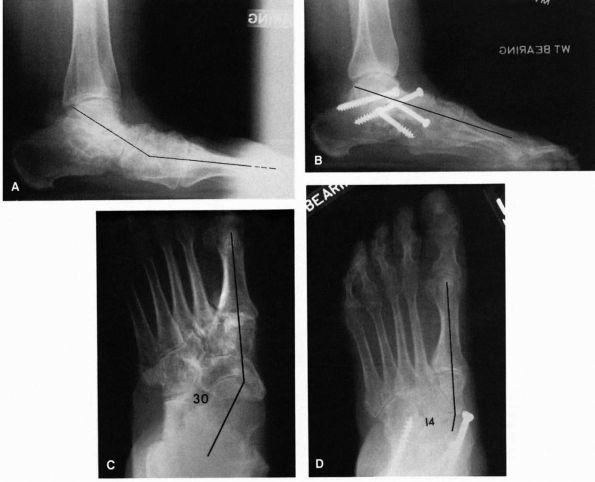

obtained to determine the source of the deformity. Primary hindfoot

and forefoot supination (Figure 21-24).

FIGURE 21-24. Radiographs of the cavus foot. (A) Marked dorsiflexion pitch of the calcaneus. Normal calcaneal pitch is 20 to 40°. (B)

FIGURE 21-25. Operative correction of a cavus foot. (A) Preoperative deformity demonstrating the increased dorsiflexion pitch of the calcaneus and mild equinus of the forefoot. (B)

Postoperative radiograph after a calcaneal osteotomy permitting dorsiflexion of the proximal fragment, dorsiflexion osteotomy of the first metatarsal, release of the plantar fascia, and fusion of the interphalangeal joint of the great toe. The longitudinal arch has been lengthened as a result of this procedure. (Mann RA, Coughlin MJ. The Video Textbook of Foot and Ankle Surgery. St Louis: Medical Video Productions, 1991) |